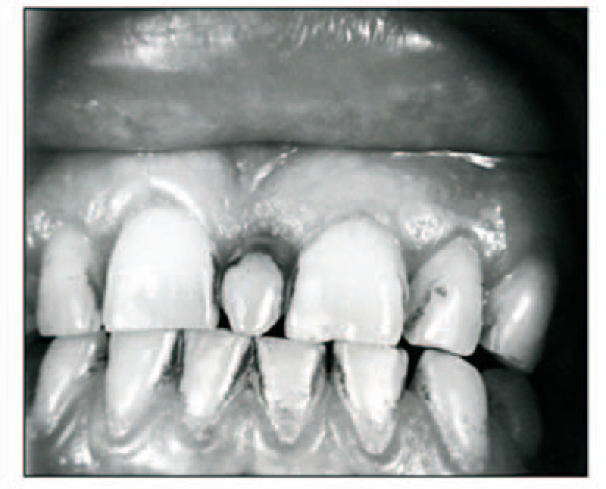

Mesiodens

Mesiodens between centrals